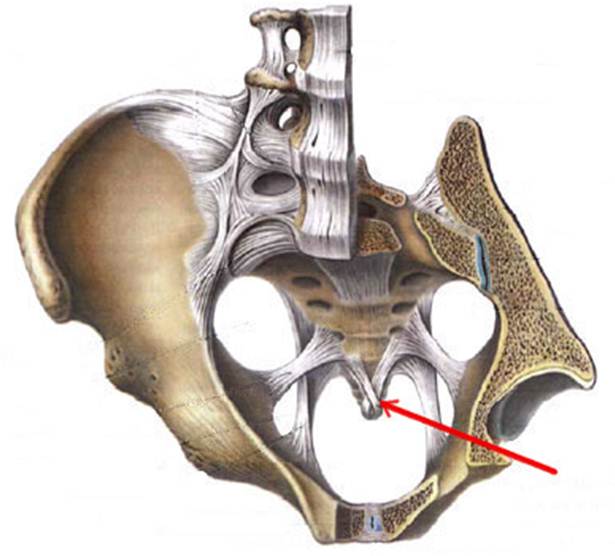

S: Стрелка указывает на Conjugata vera

S: Стрелка указывает на Conjugata diagonalis

S: Стрелка указывает на лобковый симфиз (русский язык).